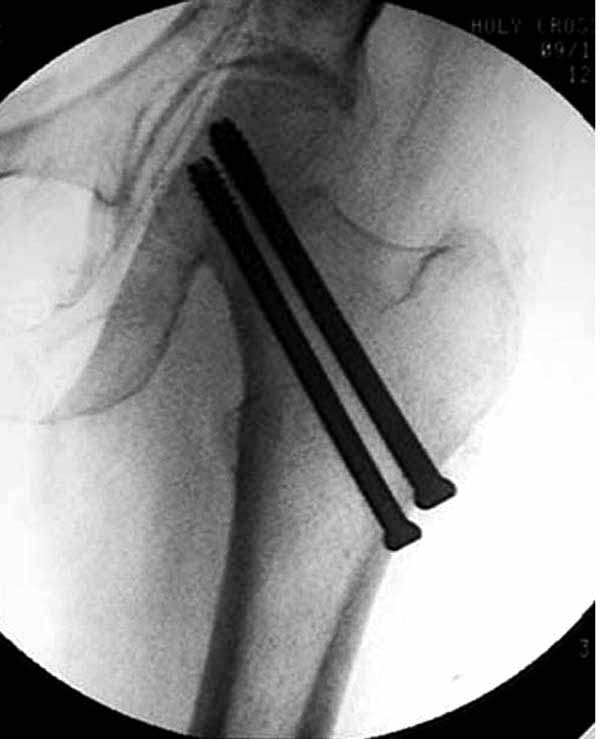

Пациентка Ш. 76 лет, 11 дней назад прооперирована по поводу вколоченного субкапитального перелома шейки левой бедренной кости, 3-мя канюлированными винтами. Вчера пациентка упала в палате. И вот результат- подимплантатный подвертельный перелом левой бедренной кости. Уважаемые коллеги, пожалуйста посоветуйте какой метод дальнейшего лечения предпринять дальше.Соматически пациента повышенного питания, страдает варикозной болезнью нижних конечностей.Из предложенных вариантов коллег - целллокастовая укороченная кокситная повязка, скелетное вытяжение сроком на 40-45 суток - отпали сразу, так как необходимо активизация пациентки.На данный момент рассматриваем следующие варианта реостеосинтеза:(наличие технических возможностей) 1. Длинная Gamma 3 Stryker (с предварительной интраоперационной фиксацией головки спицами).2. Трохантерный штифт DePuy с 2-мя метафизарными винтами в проксимальном отделе, (также с интраоперационной фиксацией головки спицами. Очень настораживает стабильность фиксации с проксимальном отделе с связи с выборкой костной ткани ранее находящимися там канюлированными винтами. Сейчас пациентка находится на скелетном вытяжении, с дисциплинирующим грузом. Операция планируется после праздников. Заранее извиняемся за качество и неполное соответствие проекций на R-ммах (R-служба отдельная песня). При интраоперационном ЭОП-контроле винты в аксиальной проекции разнесены по шейке.

два в нижней части шейки. Более стабильная структура как раз обратная: два шурупа в проксимальной части шейки , и не дальше центральной части головки, иначе есть риск пенетрации. дистальный винт мог бы быть выше уровня малого вертела. Его дистальное расположение описано с увеличенным риском послеоперационного перелома.

Как отметили коллеги, необходимо обратить внимание на последовательность введения каннюлированных шурупов. Рекомендуется введение в форме “V”, т.е основанием вниз, потому что в другой последовательности за счет увеличения стресса латерального кортекса имеется риск перелома. За редким исключением удается установить Guide wire с первой попытки и многоразовые пробы спицей увеличивают стресс. Небольшая травма может привести к перелому.

Работа Burstein AH and Wright TM: Fundamentals of Orthopaedic Biomechanics. Williams & Wilkins, Baltimore, pp. 160-169, 1994 доказывает, что шурупы, введенные на уровне малого вертела или ниже, приводят к осложнению. Введенные шурупы под 135 и больше градусов в 20% осложнились подвертельными переломами бедра.